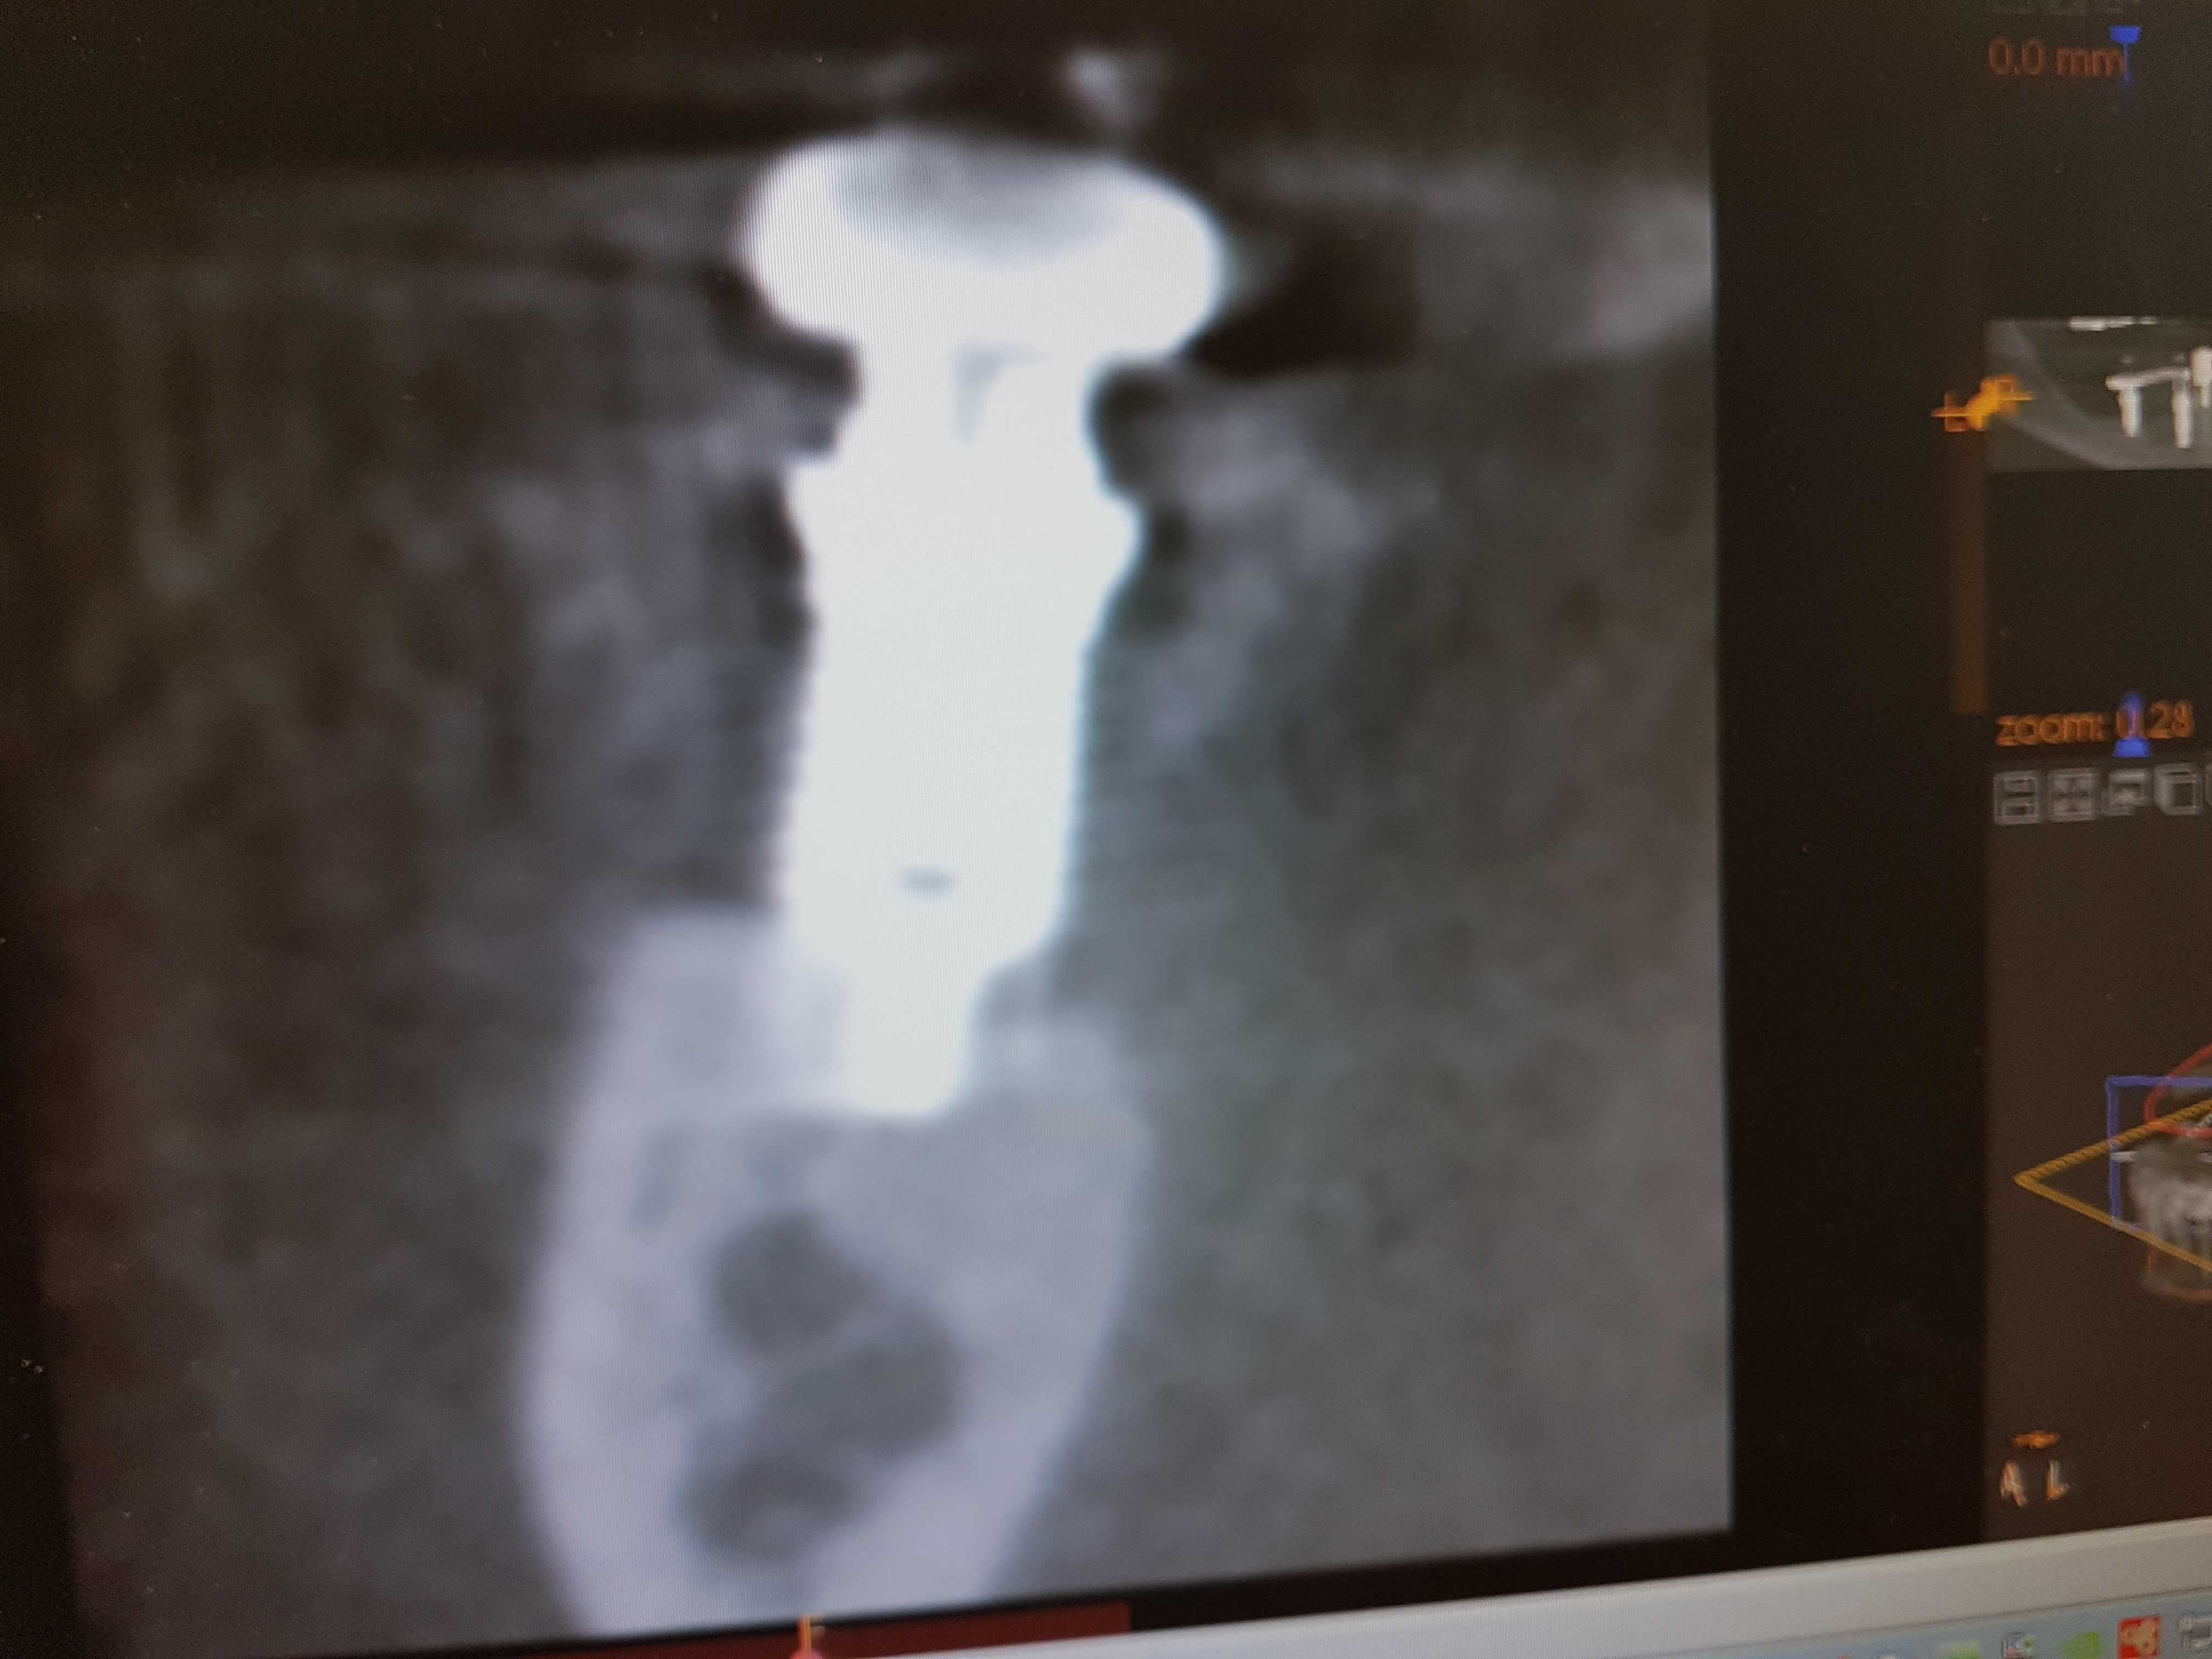

j'ai revu le patient la semaine dernière qui voulait que je prenne la suite . j'ai fait un scan et voilà ce que çà donne .